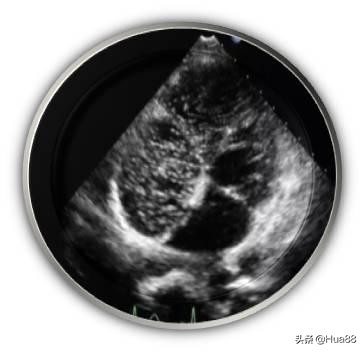

相关检查 医生如怀疑或排查患者是否存在卵圆孔未闭,通常会完善以下检查。由于超声心动图可以直观地显示房间隔解剖结构及心脏内血流分流情况,因此超声心动图是卵圆孔未闭的最 佳诊断检查。 临床上常用的超声心动图包括经胸超声心动图(TTE)、经食管超声心动图(TEE)和经颅多普勒超声声学 造影(cTCD)。 经胸超声心动图(TTE) 性价比高,操作简单、无痛苦,但该检查会受到肥胖和肺气过多等因素的干扰,检出率不高,且难以准确测 量未闭的卵圆孔大小,一般应用于儿童及部分成年人。 经胸超声心动图声学造影(cTTE)可以提高检出率,了解患者有无心脏内血液异常分流。操作时需要静脉注 射声学造影剂。 经食管超声心动图(TEE) 是诊断卵圆孔未闭的“金标准”和首选方法。该检查可以指导医生对卵圆孔未闭进行分类,从而指导治疗。 该检查属于半创伤性检查,操作过程中患者比较痛苦,类似于胃镜检查,插管会造成患者恶心、呕吐等不 适。检查前后患者须禁食、禁水。 经食管超声心动图声学造影(cTEE)亦可用于判断心脏内血液异常分流情况。 此外,三维经食管超声心动图(三维TEE)能够为二维TEE图像提供有力补充,帮助医生了解实时未闭卵圆 孔的态势,更有利于指导治疗。 经颅多普勒超声声学造影(cTCD) 简单、无创、安全。检查心脏内血液有无分流的一种常用方法,但是不能定性诊断卵圆孔未闭。作为卵圆孔 未闭筛查的一种方法,通常需要进一步进行经胸超声心动图(TTE)、经食管超声心动图(TEE)等检查作 为补充。 心导管检查、对比分析双源CT冠状动脉成像和心脏磁共振成像(MRI)可以发现卵圆孔未闭,但费用较高, 敏感性相对较差,临床较为少用。

右心声学造影+发泡实验